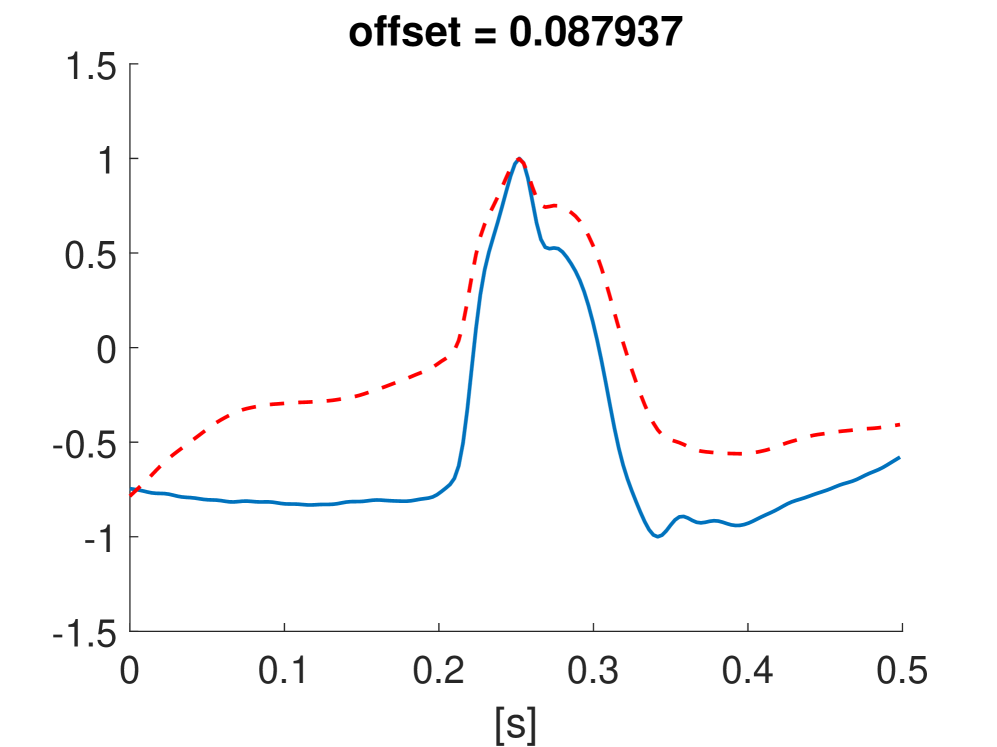

Fig. 10 shows the result in input space of moving along the first principal components in the latent feature space. As original base point we take a normal beat signal, i.e. corresponding to a hidden unit on the bottom right of Fig. 9(a). The smooth transition between the beat patterns allows for interpretation of the first principal components. This allows a clinical expert to understand on what basis the paced beats are separated by the principal components and if this basis has a physiological meaning. In order to investigate the separated region of the latent space at the top of Fig. 9(b) we start from a paced beat pattern and vary along the third principal component. This allows us to see which sort of heartbeat patterns are responsible for this specific distribution in the latent space.